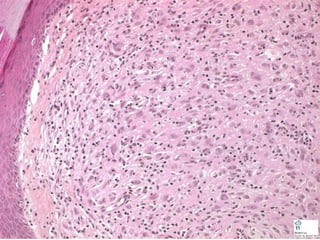

• #54 By far, the commonest malignancy of skin, BCC, i.e., Basal Cell Carcinoma, typical appearance. Note the PERIPHERAL PALISADING!!! PALISADING!!! PALISADING!!! PALISADING!!!

• #55 Merkel cell tumor, very highly malignant RARE and usually fatal, looks EXACTLY like a small cell carcinoma of the lung? Ans: yes.